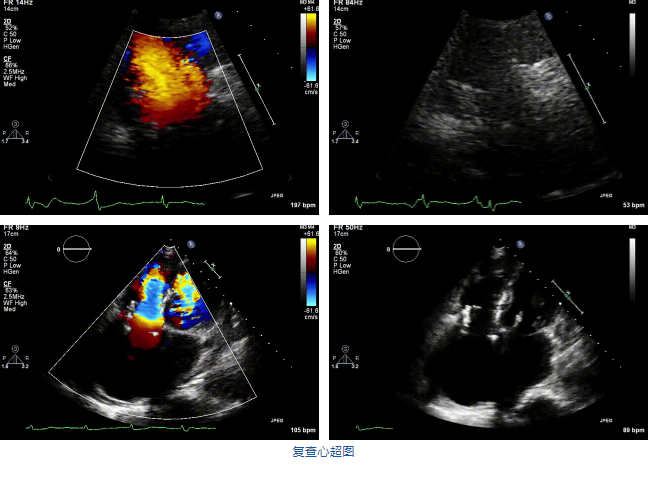

結(jié)合術(shù)前CT評估結(jié)果,葛均波院士團(tuán)隊(duì)最終決定選用LuX-Valve Plus 50mm和55mm兩種型號(hào)的瓣膜,并于2021年11月30日順利完成LuX-Valve Plus經(jīng)血管三尖瓣置換術(shù),手術(shù)室即刻拔除氣管插管,術(shù)后第二天轉(zhuǎn)出心內(nèi)科監(jiān)護(hù)室,下床活動(dòng)。術(shù)后患者三尖瓣反流癥狀得到顯著改善,復(fù)查心超結(jié)果顯示人工三尖瓣瓣膜支架固定穩(wěn)定,瓣葉關(guān)閉形態(tài)未見異常,未見明顯反流。